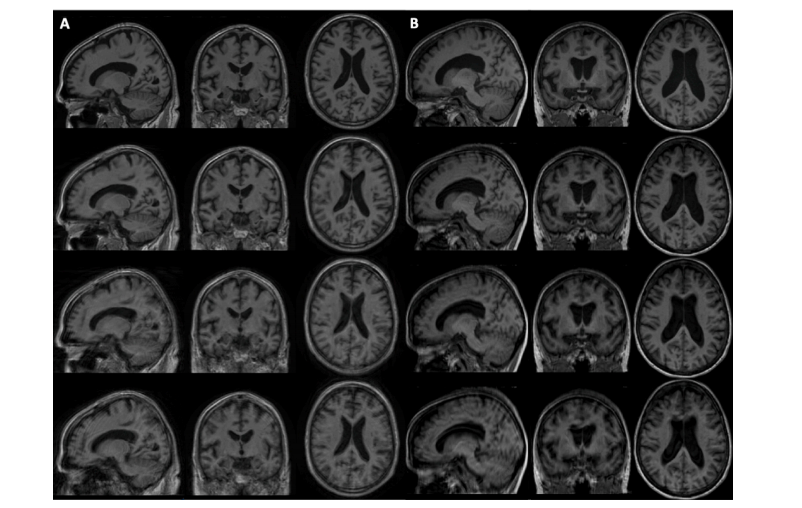

Fig. 2. Example of motion simulation on brain MRI using the k-space (A) and the image (B) based approach with different translation and rotation ranges. From top to bottom:motion-free MRI, MRIs corrupted with a rotation of 3◦ , 5◦ and 7◦ and a translation of 3 mm, 5 mm and 7 mm.

图2. 使用基于k空间(A)和图像(B)的方法对脑部MRI进行运动模拟的示例,应用了不同的平移和旋转范围。自上而下:无运动伪影的MRI,分别受到3°、5°和7°旋转以及3 mm、5 mm和7 mm平移影响的MRI。